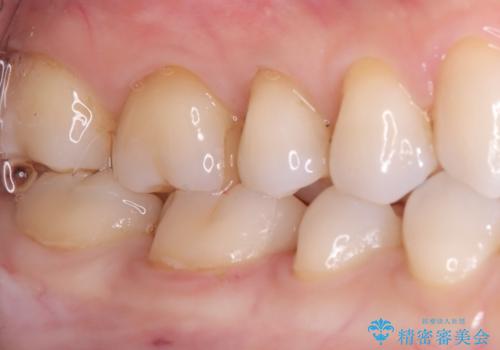

- 主訴:右下の奥歯がたまに冷たい物や甘いものでしみる

右下6番目の歯に大きめのう蝕を認め、形態の再現性を考えインレーでの治療となりました。

右下6の近心にう蝕が認められう蝕の範囲が大きかったため、歯冠形態の再現性の高いインレーでの修復とし、材質は審美性、清掃性に優れたセラミックを選択しました。